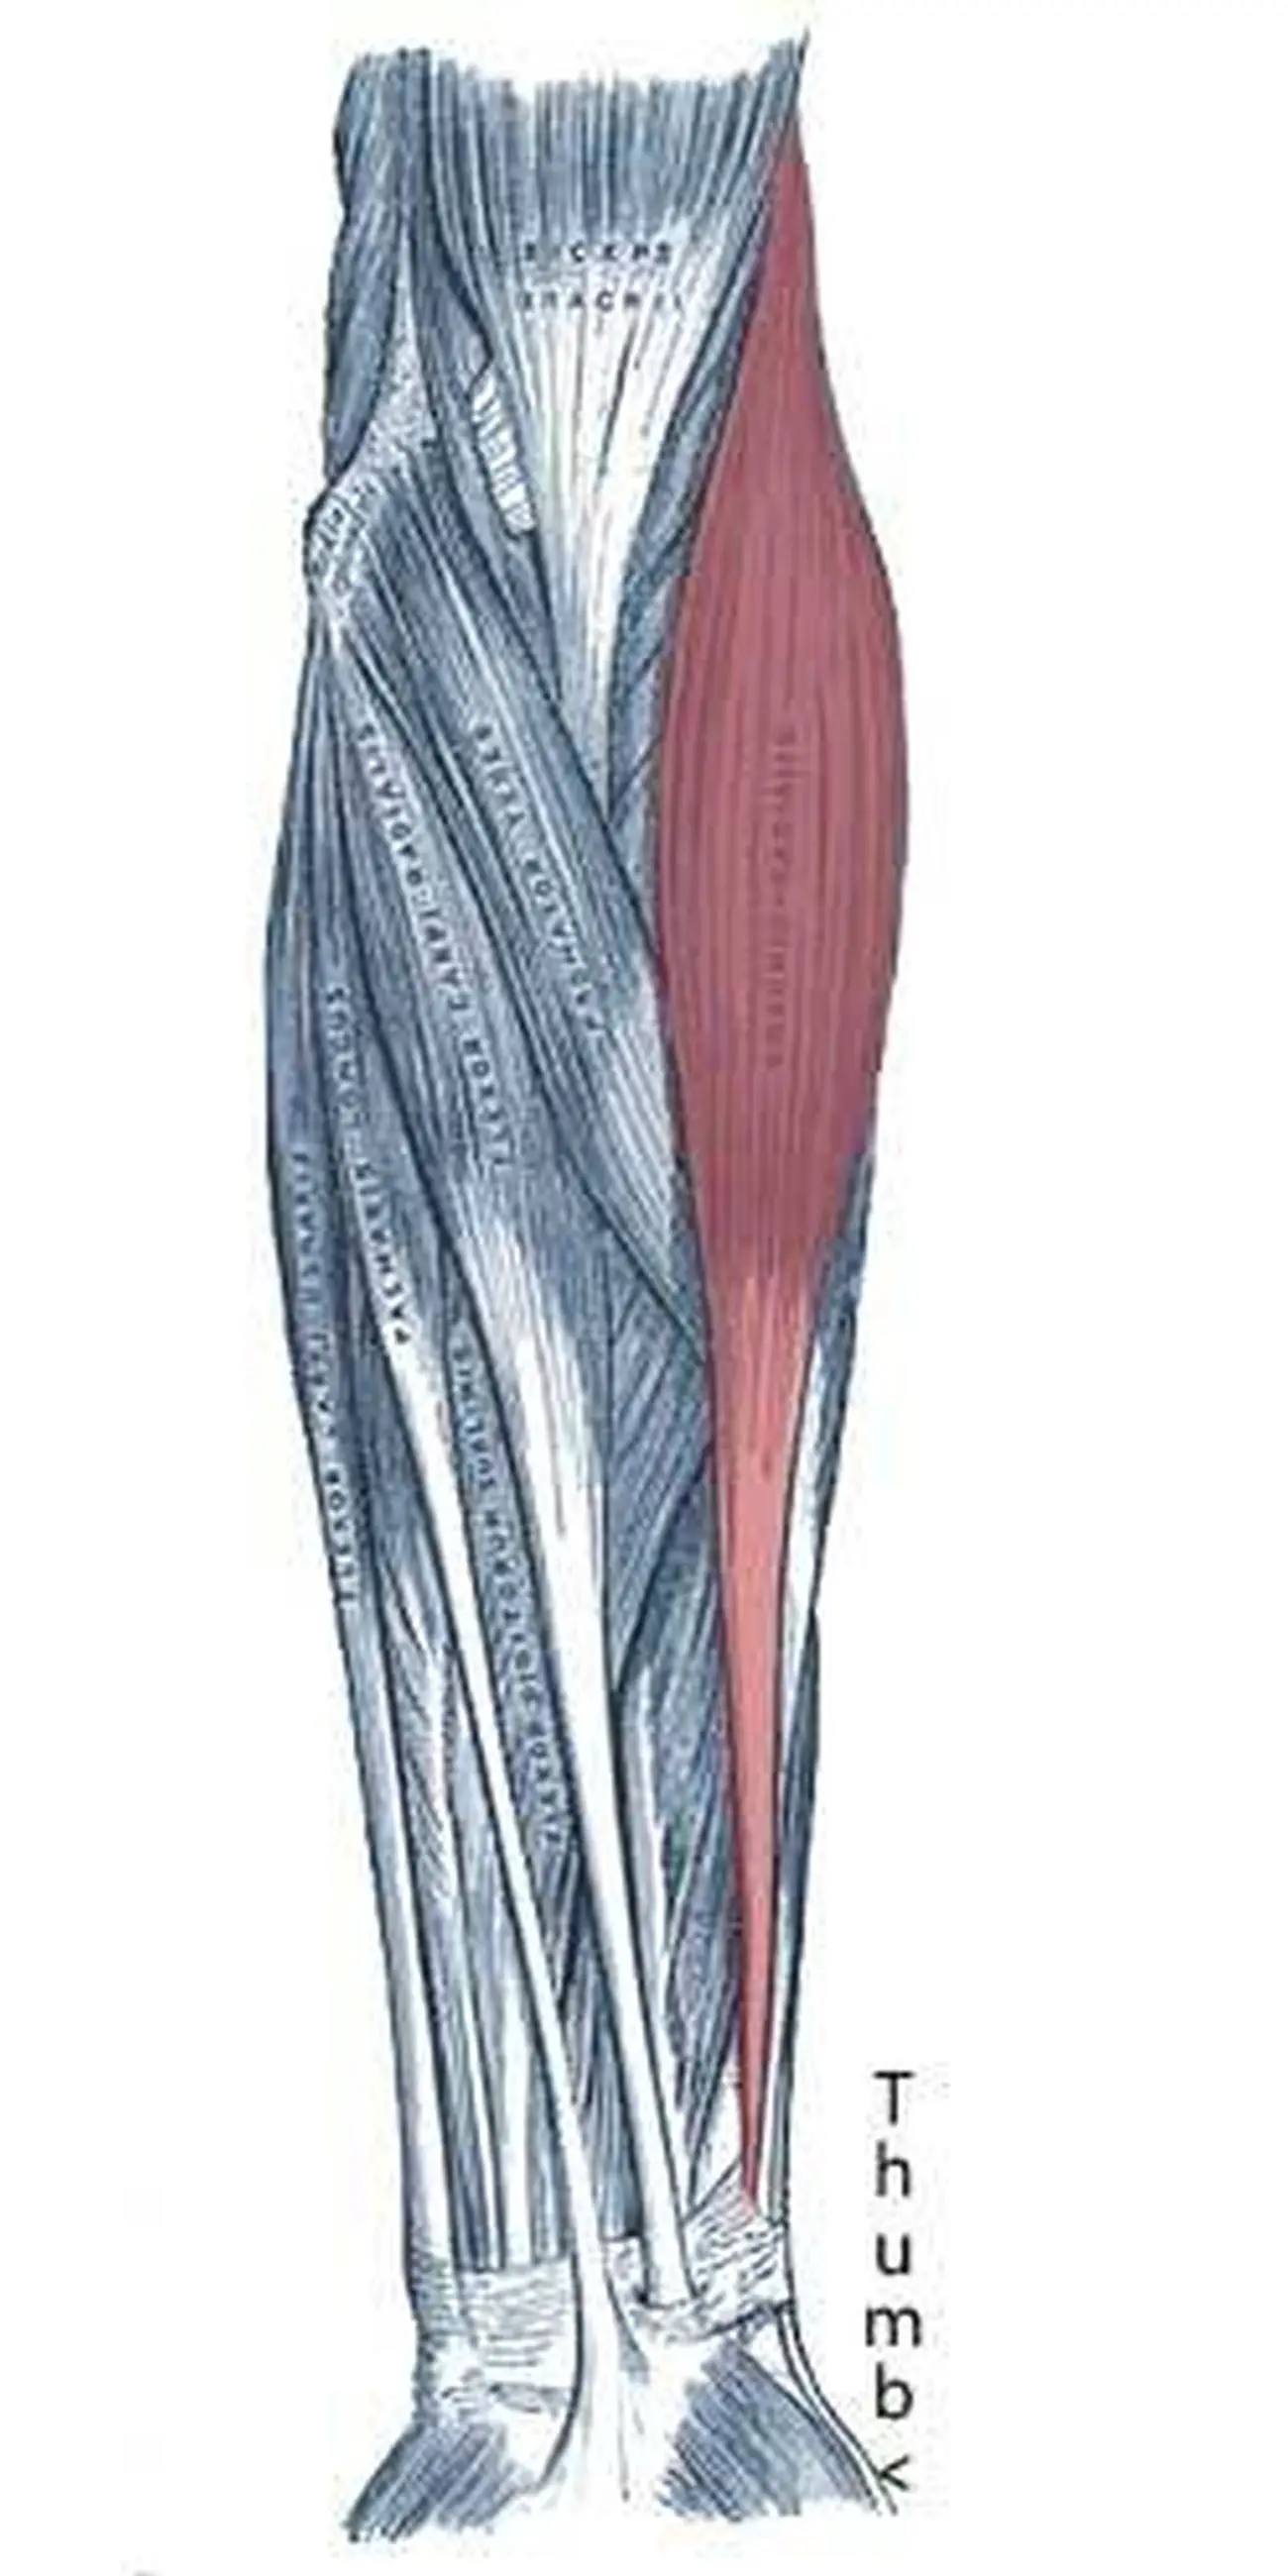

Анатомия и функции мышцы brachioradialis